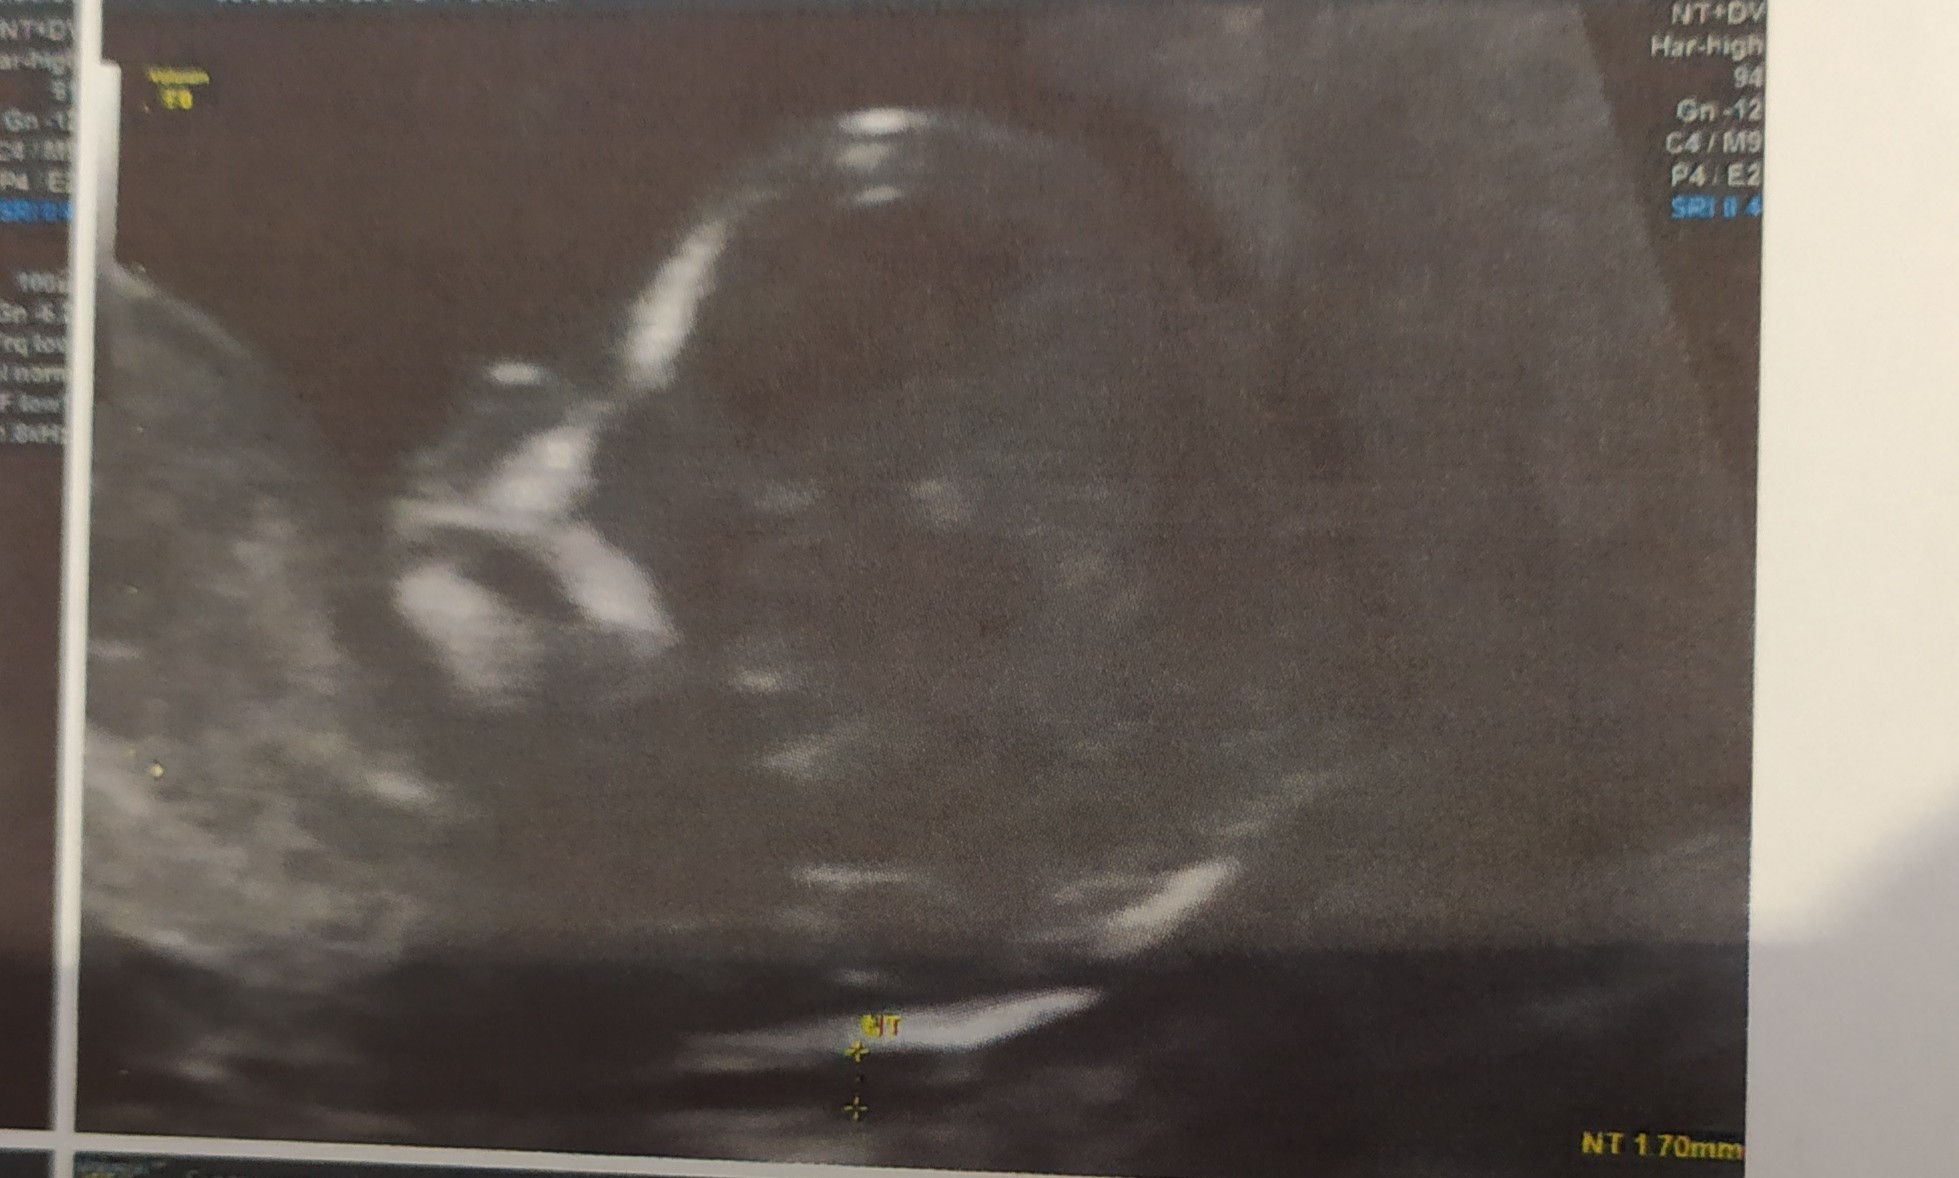

Hej dziewczyny ja po, prenatalnych :) dzidziuś ma 7cm z OM 6.04 ale z USG 5.04. Ale masakra musiałam, wyjść gabinetu iść zjeść coś słodkiego II napełnić pęcherz i wrócić bo, maluch się obrócić niechcial, płci nie powiedział. NT 1,7mm wszystko prawidłowo, nosek jest :) wyniki z krwi 1:19035 . Kolejne badania prenatalne 30.11 to będzie 22tc

• IMG_20200928_143519.jpg

IMG_20200928_143519.jpg

314,2 KB · Wyświetleń: 87

• IMG_20200928_143248.jpg

IMG_20200928_143248.jpg

427,1 KB · Wyświetleń: 98